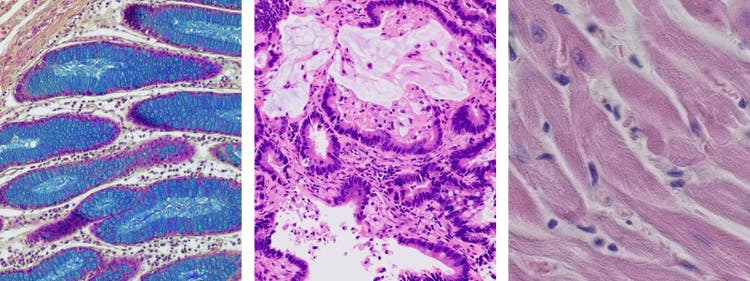

Brightfield microscopy is one of the most common types of microscope observation methods used in biology and medicine. It is a simple and reliable method that enables scientists to study and visualize samples in detail. In this post, we will discuss what brightfield microscopy is, how it works, and its advantages and limitations.

Brightfield microscopy, also known as a compound light microscopy, uses light to illuminate a sample and create an image. The sample is placed on a glass slide and illuminated by a light source, typically a halogen lamp or a light-emitting diode (LED) light. The light passes through the sample, and an objective magnifies the image and projects it onto an eyepiece or a camera. The sample appears dark against a bright background, hence the name “brightfield.”

Brightfield microscopy can be used to study a wide range of samples, from cells and tissues to minerals and fibers. This makes it a versatile tool for many fields of research and industry.

The main limitation of brightfield microscopy is that it only works well for samples that have high contrast with their backgrounds. For example, it is difficult to study samples that are transparent or the same color as the background. Additionally, samples that are not properly prepared or stained may not be visible under a brightfield microscope.